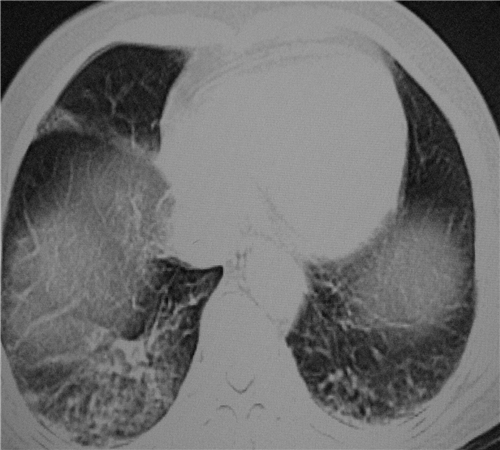

标题: CT26849:女67岁反复胸痛两天余,临床考虑夹层。

右肺感染,未见夹层。

既然考虑夹层,建议强化!另:右下肺感染!

1)右肺感染性病变。2)建议行ct增强扫描或mri检查排除主动脉夹层。

双下肺感染,右侧显著。有无夹层,增强扫描后再诊断。

1.考虑双肺感染,右侧为重;2.建议ct增强或mri排除主动脉夹层